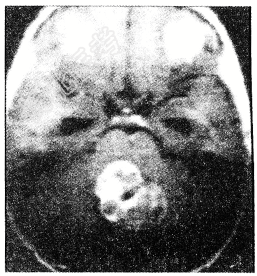

- 单项选择题下列哪一项不符合髓母细胞瘤(如图所示)表现

A、对放疗不敏感

B、主要发生于小儿,是儿童第2位常见肿瘤

C、好发于小脑蚓部

D、髓母细胞瘤起源于后髓帆外颗粒层的残余胚细胞

E、病情发展较快,一般为半年至1年